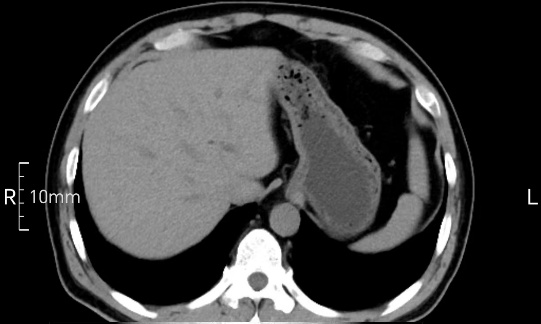

看看下面三幅便知遵醫(yī)囑的重要性。

完美禁食且喝飽飽,胃壁完美展現(xiàn)。

CT檢查前的“禁食”和“喝飽”,看似矛盾,實(shí)則合情合理,分工合作:空腹:是為了讓上腹部(肝膽胰脾腎等)的圖像清晰無干擾,并保障檢查安全。喝水:有效的充盈胃部和、腸道使圖像清晰呈現(xiàn)。兩者巧妙配合,都是為了給您一個(gè)最精準(zhǔn)的診斷結(jié)果。